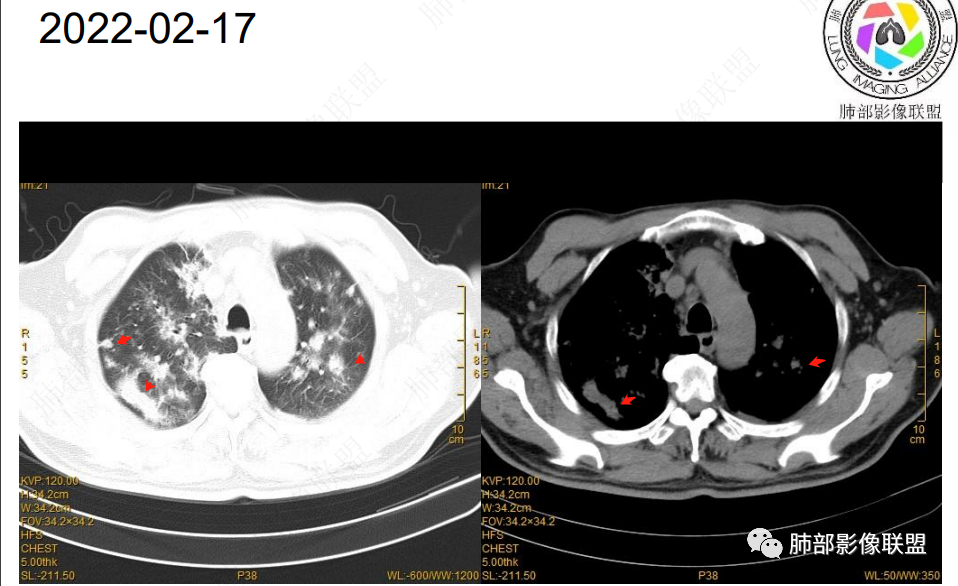

2022.2.17CT显示两肺中内带多发结节影、斑片影、条索影,部分病灶侧向融合与胸膜平行。部分病灶沿着支气管血管束分布、其内支气管稍扩张。部分病灶呈反晕征。大部分病灶边界显示清晰,部分病灶周围可见边界不清的GGO。2022.4.12CT显示两肺中内带多发结节影、条索状、条带状高密度影,边界收缩平直凹陷,大部分病灶沿着支气管血管束分布,亦有位于胸膜下侧向融合与胸膜平行的病灶。总体与第一次CT对比两肺病灶明显吸收。

老年男性,两肺多发病灶,整体呈OP样改变,至于是原发性还是继发性的OP,需要临床鉴别。此病例穿刺结果是隐球菌。该病例CT上缺乏隐球菌典型的“在那遥远的胸膜下,多个蘑菇兄弟,可以侧向融合呈长串状与胸膜平行”影像表现,更多是OP样改变,仅凭临床表现或影像资料诊断隐球菌难度比较大。当然也不除外二元论,导致隐球菌的影像表现被掩盖。